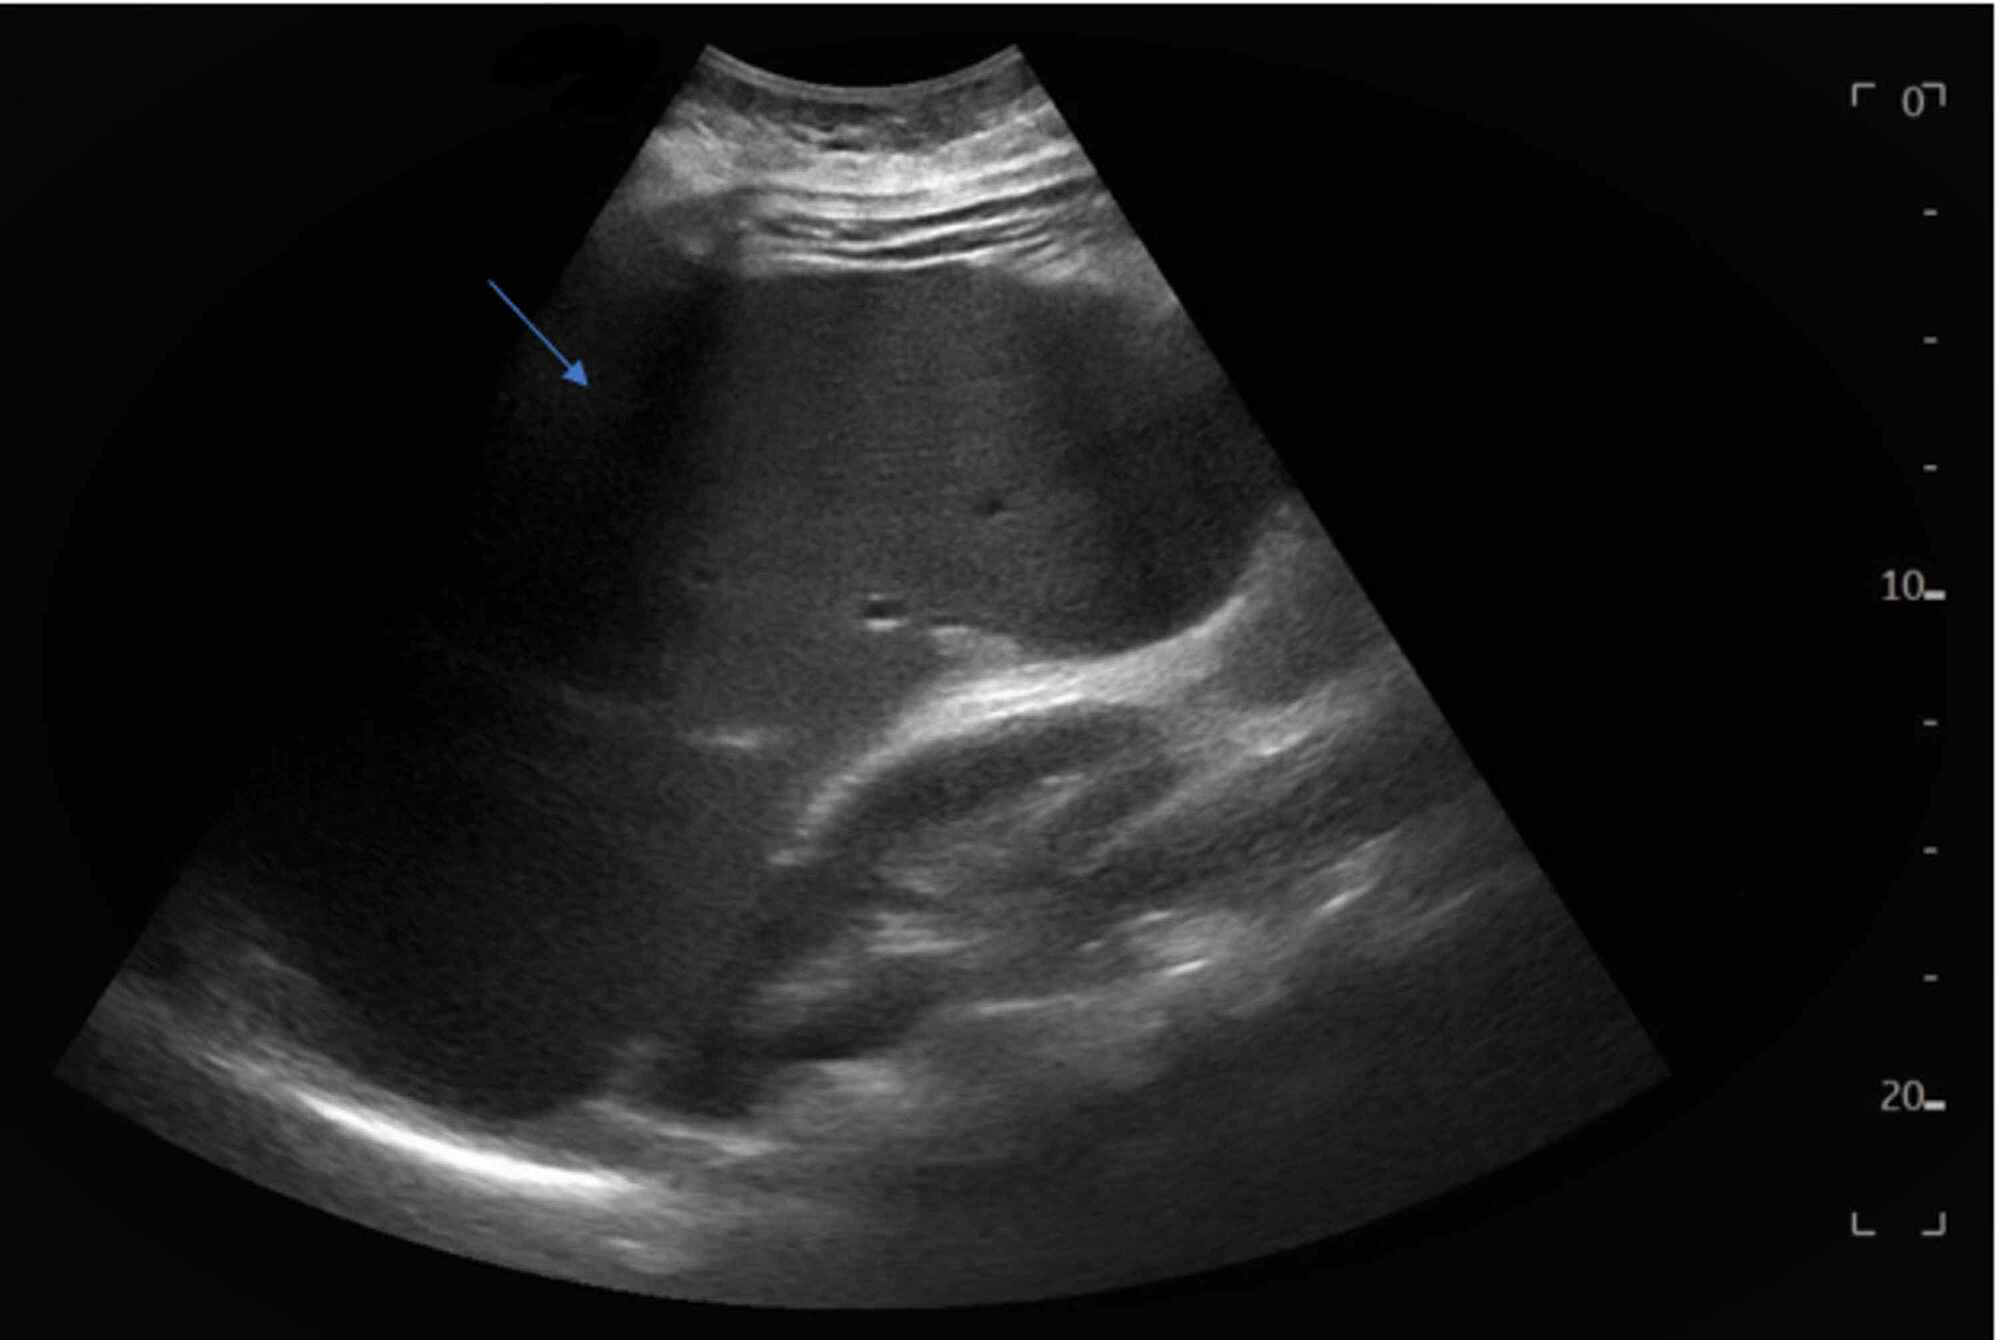

Ultrasound Hepatitis Radiology Imaging Autoimmune Hepatitis Ultrasound Findings liver histology is mandatory for the diagnosis of autoimmune hepatitis. the diagnosis of autoimmune hepatitis (aih) is based on a combination of clinical, biochemical, immunological, and. Assessing the degree of inflammatory activity such as interface and lobular. ultrasound findings in autoimmune hepatitis (aih) have not been reported systematically so far. the most common physical findings in. Autoimmune Hepatitis Ultrasound Findings.

Ultrasound findings in autoimmune hepatitis Autoimmune Hepatitis Ultrasound Findings the diagnosis of autoimmune hepatitis (aih) is based on a combination of clinical, biochemical, immunological, and. autoimmune hepatitis is a chronic, inflammatory disease of the liver that is characterized by circulating. ultrasound findings in autoimmune hepatitis (aih) have not been reported systematically so far. liver histology is mandatory for the diagnosis of autoimmune hepatitis. the. Autoimmune Hepatitis Ultrasound Findings.